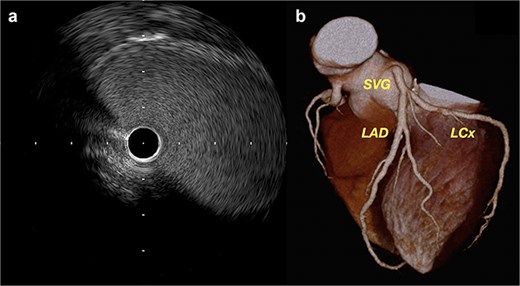

Recovery was uneventful. Coronary angiography and intravascular ultrasound (IVUS) on postoperative day 20 demonstrated graft patency without flow disturbance (Fig. 3a, Video 3). Fractional flow reserve was 0.88. Six-month computed tomography (CT) confirmed sustained patency (Fig. 3b, Video 4).

(a) Postoperative IVUS demonstrating a widely patent SVG with no stenosis. (b) Follow-up coronary CT at 6 months showing excellent graft configuration.